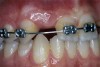

Before the day of surgery, the patient was seen by the orthodontist for the removal of the orthodontic brackets. The patient still was not pleased with the position of the two centrals, and it was determined that this would be addressed after implant placement (Figure 13A). The anatomical variations of the crestal tissue and lack of interdental papilla can be appreciated in the close-up views of the right and left sites (Figure 13B and 13C). There were no surprises on the day of surgery as all of the decisions were made during the planning phase, before the scalpel ever touched the patient. The occlusal view of the CT 3D model revealed the wider alveolar ridge on the right side and thinner crest on the left side (Figure 14A). This was confirmed when the full thickness mucoperiosteal flaps were elevated, and the underyling bone revealed (Figure 14B). The tooth-borne templates were designed to facilitate the drills and drilling sequence specific to the diameters of the predetermined implants (Figure 15A). Each template contained an embedded 5-mm long stainless steel tube, which was approximately 0.2-mm wider than each drill (just wide enough to allow for the drills to rotate freely). Once positioned over the natural teeth, the template was secure and offered precision accuracy in transferring the implant locations from the original software-designed plan, allowing the potential for internal and external irrigation (Figure 15B). The 3.7-mm diameter Tapered Screw-Vent implant drilling sequence requires three drills: pilot, intermediate, and final sizing. Thus, three separate templates were fabricated to a.commodate these sizes. The templates were removed easily and replaced with the next sequential size in less time than it takes to change the drill on the surgical handpiece. After the osteotomies had been.completed, the implants were delivered to the site (Figure 16A and Figure 16B). For this internal hex connection implant, the author r.commends that the flat of the antirotational hex be positioned to the facial for proper orientation of the restorative.components (Figure 17A). Preprepared margins were created from a milled titanium fixture mount transfer post, which was delivered to the implant as support for an immediate transitional restoration. The facial “dot” helped confirm the orientation of the abutment to the facially positioned flat side of the internal hex connection (Figure 17B). Before cementation of the transitional acrylic restorations, a closed-tray, fixture-level impression was made, and a soft-tissue model fabricated.

Figure 13a  Before implant surgery, the orthodontic brackets were removed, revealing (A) the position of the centrals, and (B, C) the anatomical variations of the crestal tissue and lack of interdental papilla.

Figure 13a

Figure 13b  Before implant surgery, the orthodontic brackets were removed, revealing (A) the position of the centrals, and (B, C) the anatomical variations of the crestal tissue and lack of interdental papilla.

Figure 13b

Figure 13c  Before implant surgery, the orthodontic brackets were removed, revealing (A) the position of the centrals, and (B, C) the anatomical variations of the crestal tissue and lack of interdental papilla.

Figure 13c